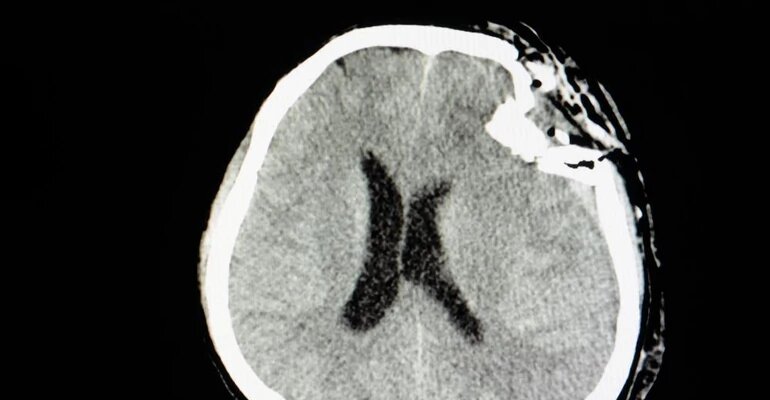

Мозг - это основной орган центральной нервной системы, благодаря которому мы можем получать, обрабатывать и генерировать раздражители. Таким образом, очевидно, что каждое его нарушение представляет собой огромную угрозу для здоровья и жизни человека. Одно из таких заболеваний, которое при отсутствии лечения приводит к летальному исходу, - это отек мозга. Это либо чрезмерное накопление жидкости в ткани мозга, вызванное повреждением гематоэнцефалического барьера, либо скопление жидкости в клетках головного мозга, характеризующееся цитотоксическим отеком.

Распространенными причинами отека мозга являются тяжелые травмы головы в результате удара о твердую поверхность или падения со значительной высоты. Как следствие этих событий происходит повышение внутричерепного давления. Набухание мозга в результате несчастного случая может сопровождать другие патологии, такие как гематомы или участки ушиба головного мозга. Также возможно, что это происходит как самостоятельное посттравматическое явление в головном мозге.